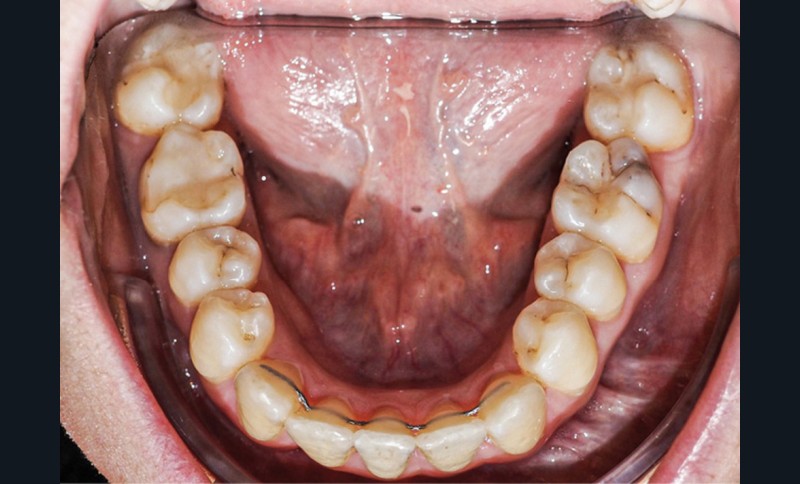

Examen endo-buccal (fig. 2a-e)

L’arcade maxillaire est parabolique, la 12 présente une légère mésio-rotation. L’arcade mandibulaire est également parabolique avec un encombrement antérieur estimé à 6 mm. On note une dyschromie de la 31, dont le test de vitalité est négatif. Le parodonte est fin.

En occlusion, on note une relation de Classe I molaire bilatérale avec un surplomb normal et une supraclusion. Les médianes incisives sont concordantes.

Les incisives maxillaires sont de forme triangulaire [1] et l’indice de Bolton est de 97 % qui traduit la présence d’une DDD par excès mandibulaire.